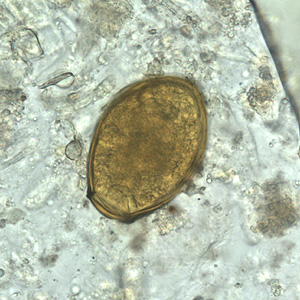

Much like a parasite fooling its host in order to survive, our beliefs seem to be able to create a way to live on often without our knowledge.